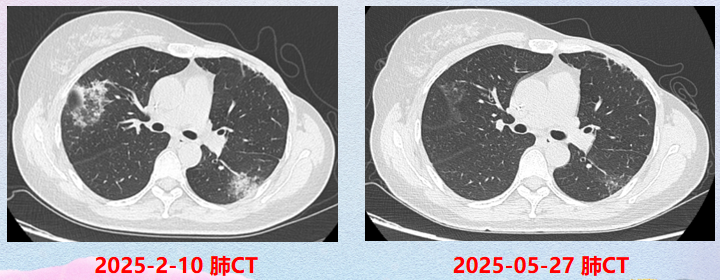

2025年2月

患者再发咳嗽、咳痰症状,遂进一步完善胸部CT:右肺上叶、左肺下叶炎症,较前新增;CRP 60.4mg/L;甲乙流新冠核酸阴性。呼吸内科会诊后,建议莫西沙星经验性抗感染治疗后复查,暂停T-DXd治疗;后续患者于当地复查,经治疗肺部感染好转后,继续T-DXd治疗。